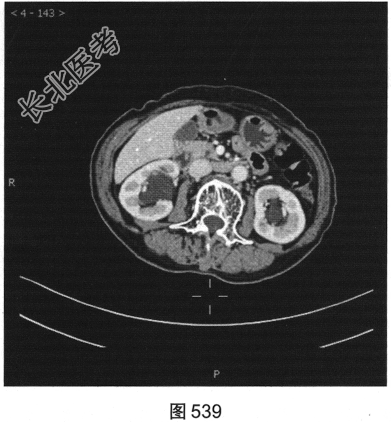

- 多项选择题3.[提示]CT平扫+增强(图538~图542)所见:双侧肾盂肾盏旁可见沿肾盂肾盏走行的多发囊样低密度灶, 未见明显强化。应考虑的鉴别诊断为( )

A、肾外肾盂旁血管病变

B、肾盂旁肿瘤性病变

C、囊性肾癌

D、肾盂旁囊肿

E、肾积水

F、肾窦内脂肪沉积症